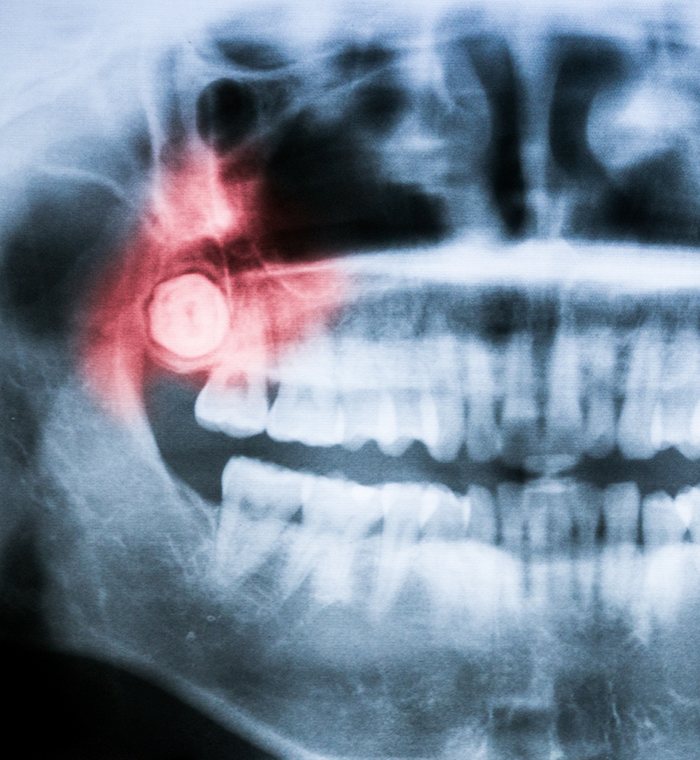

The Wisdom Tooth Extraction Process

Glamorous Smile Dental Spa is equipped with the most advanced, state-of-the-art technologies so that Dr. Alkamary can perform wisdom tooth extraction with ease. Whether it is you or your teenager who requires this procedure, she will start by making sure you are comfortable, using local anesthesia, patient-friendly amenities, and sedation if requested.

Once she determines the state of each molar, she will either remove it with a simpler process that involves elevating the tooth and using pliers to move it back and forth until it detaches, or she will opt for a surgical approach.

If the tooth cannot be seen above the gumline, it will require opening the gums and exposing the tooth and bone. To avoid causing additional damage to the bone, she will likely divide the tooth into sections for easier, less stressful removal.